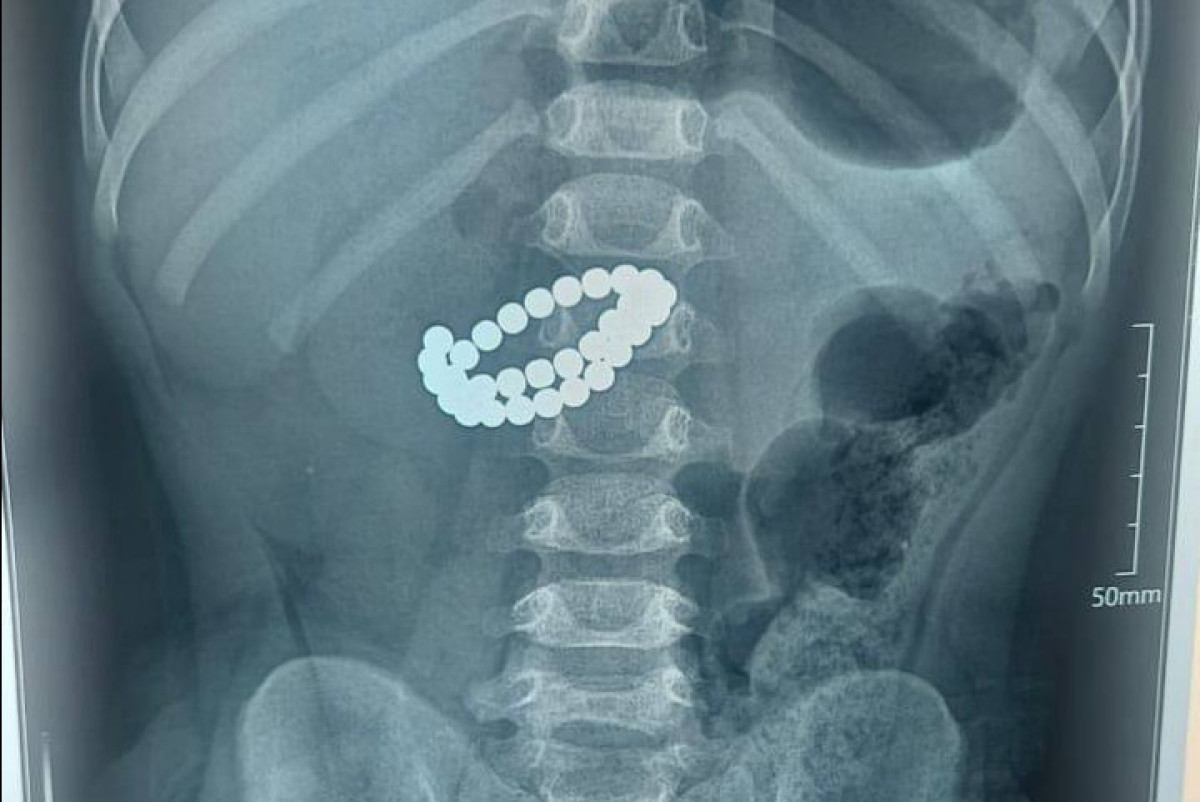

В Центре детской неотложной медицинской помощи Алматы врачи провели экстренную операцию по спасению ребёнка 1 года 9 месяцев, который проглотил 31 магнит, передает BAQ.KZ со ссылкой на управление общественного здравоохранения города.

Малыш поступил в приёмное отделение в крайне тяжёлом состоянии. После обследования медики диагностировали: инородные тела в кишечнике — 31 магнит, множественные перфорации тонкой кишки и диффузный каловый перитонит.

Единственным шансом спасти жизнь ребёнка стало срочное хирургическое вмешательство. Врачи провели срединную лапаротомию, извлекли магниты, зашили множественные перфорации, провели санацию и дренирование брюшной полости, а также трансанальную интубацию кишечника.